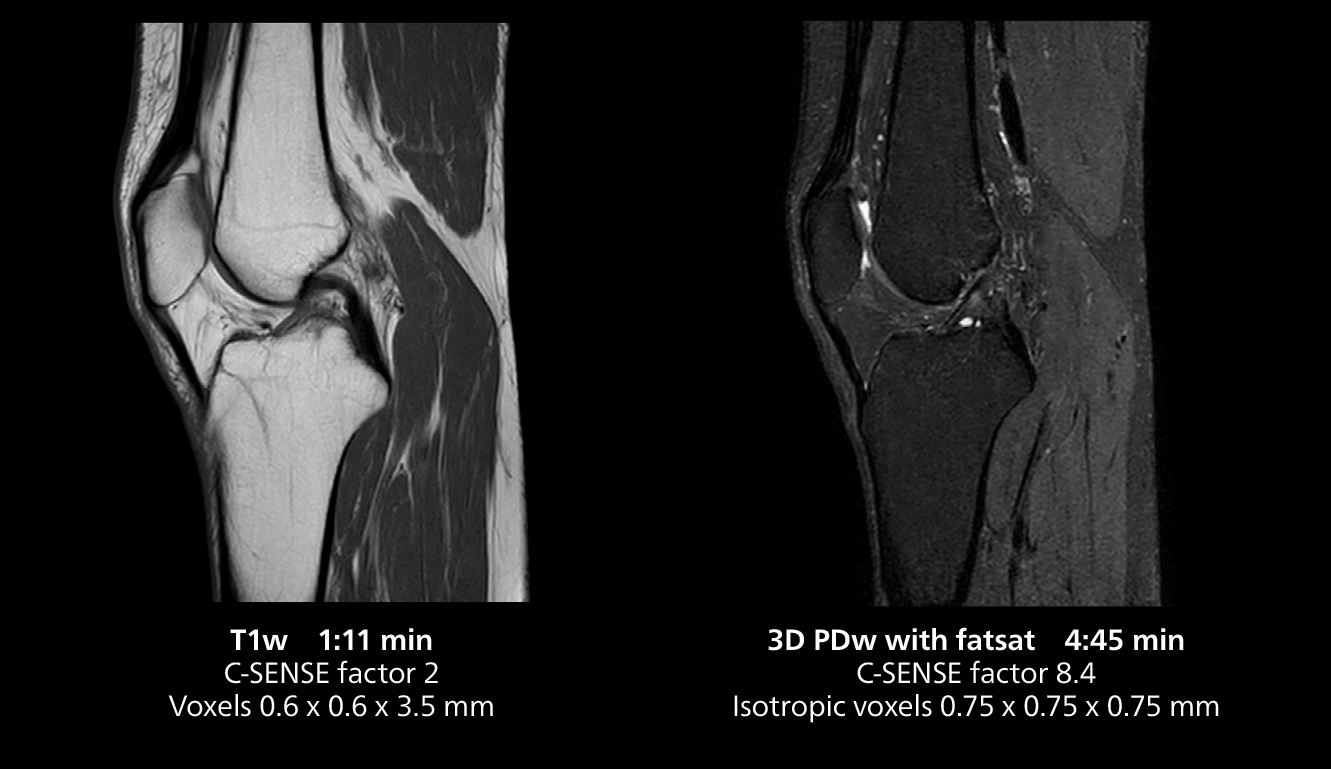

According to Dr. Gellée, the hospital conducts an average of four studies each hour, totaling about 40-45 patients per day on their MR 5300. Studies are read by approximately 50 radiologists in the Bordeaux area. Dr. Gellée is especially satisfied with the image quality of the MR system. "I obtain higher image contrast and more anatomical precision than I was used to,” she says. “When I am able to choose, I request that studies be done on this system, because I get better anatomical image quality. For example, in the knees, I can get great images of the meniscus. To me, it looks as pretty as 3T.”

3D knee imaging

The isotropic high resolution 3D sequence in this MRI case allows for reformatting to obtain other orientations with high quality. Acquired on the MR 5300 system.